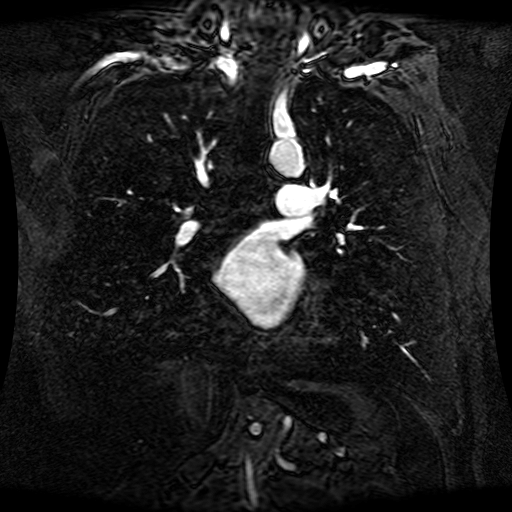

These magnetic resonance angiography (MRA) images show coronal slices acquired from consecutive anteroposterior positions within the torso. The study was performed on a 1.5T General Electric (GE) Signa imaging system with gadolinium-contrast-enhancement for visualization of the cardiopulmonary vasculature. The pulse sequence used was a 3D time-of-flight fast spoiled gradient recalled acquisition in steady state (FSPGR, TR=6.3, TE=1.4, NEX=1, FOV = 40cm, slice thickness = 1.2mm).

This sample image contains 76 frames. It is available in DICOM format (E1154S7I.dcm), as an animated GIF (E1154S7I.gif), as .ogg, .mp4, .webm, and .swf animations (one of which is shown above), or as individual PNG-format frames (see below).